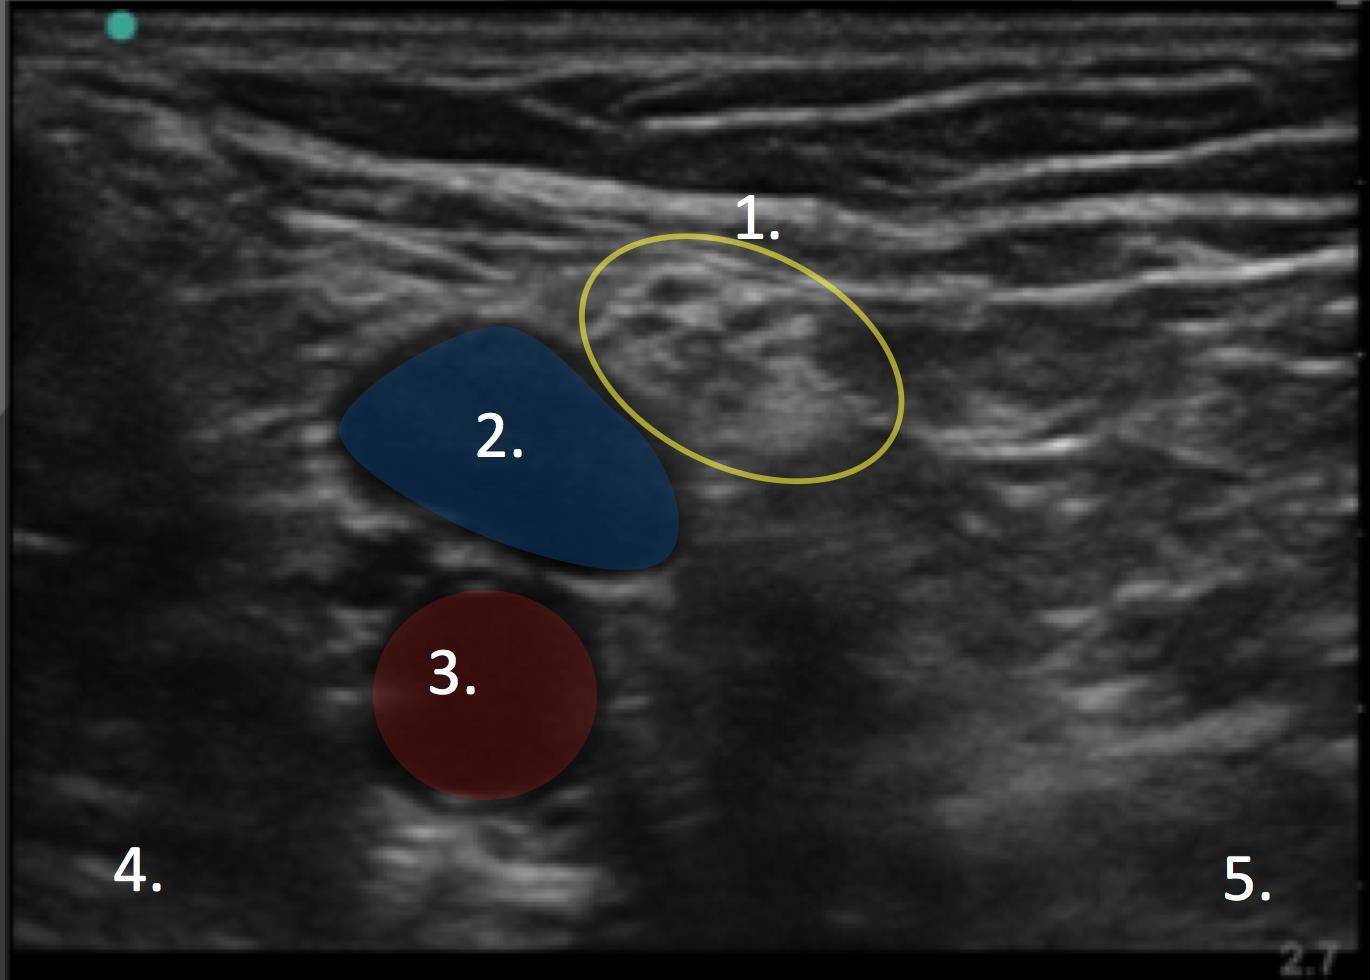

膝窩のイメージ

脛骨神経

膝窩静脈

膝窩動脈

外側

内側